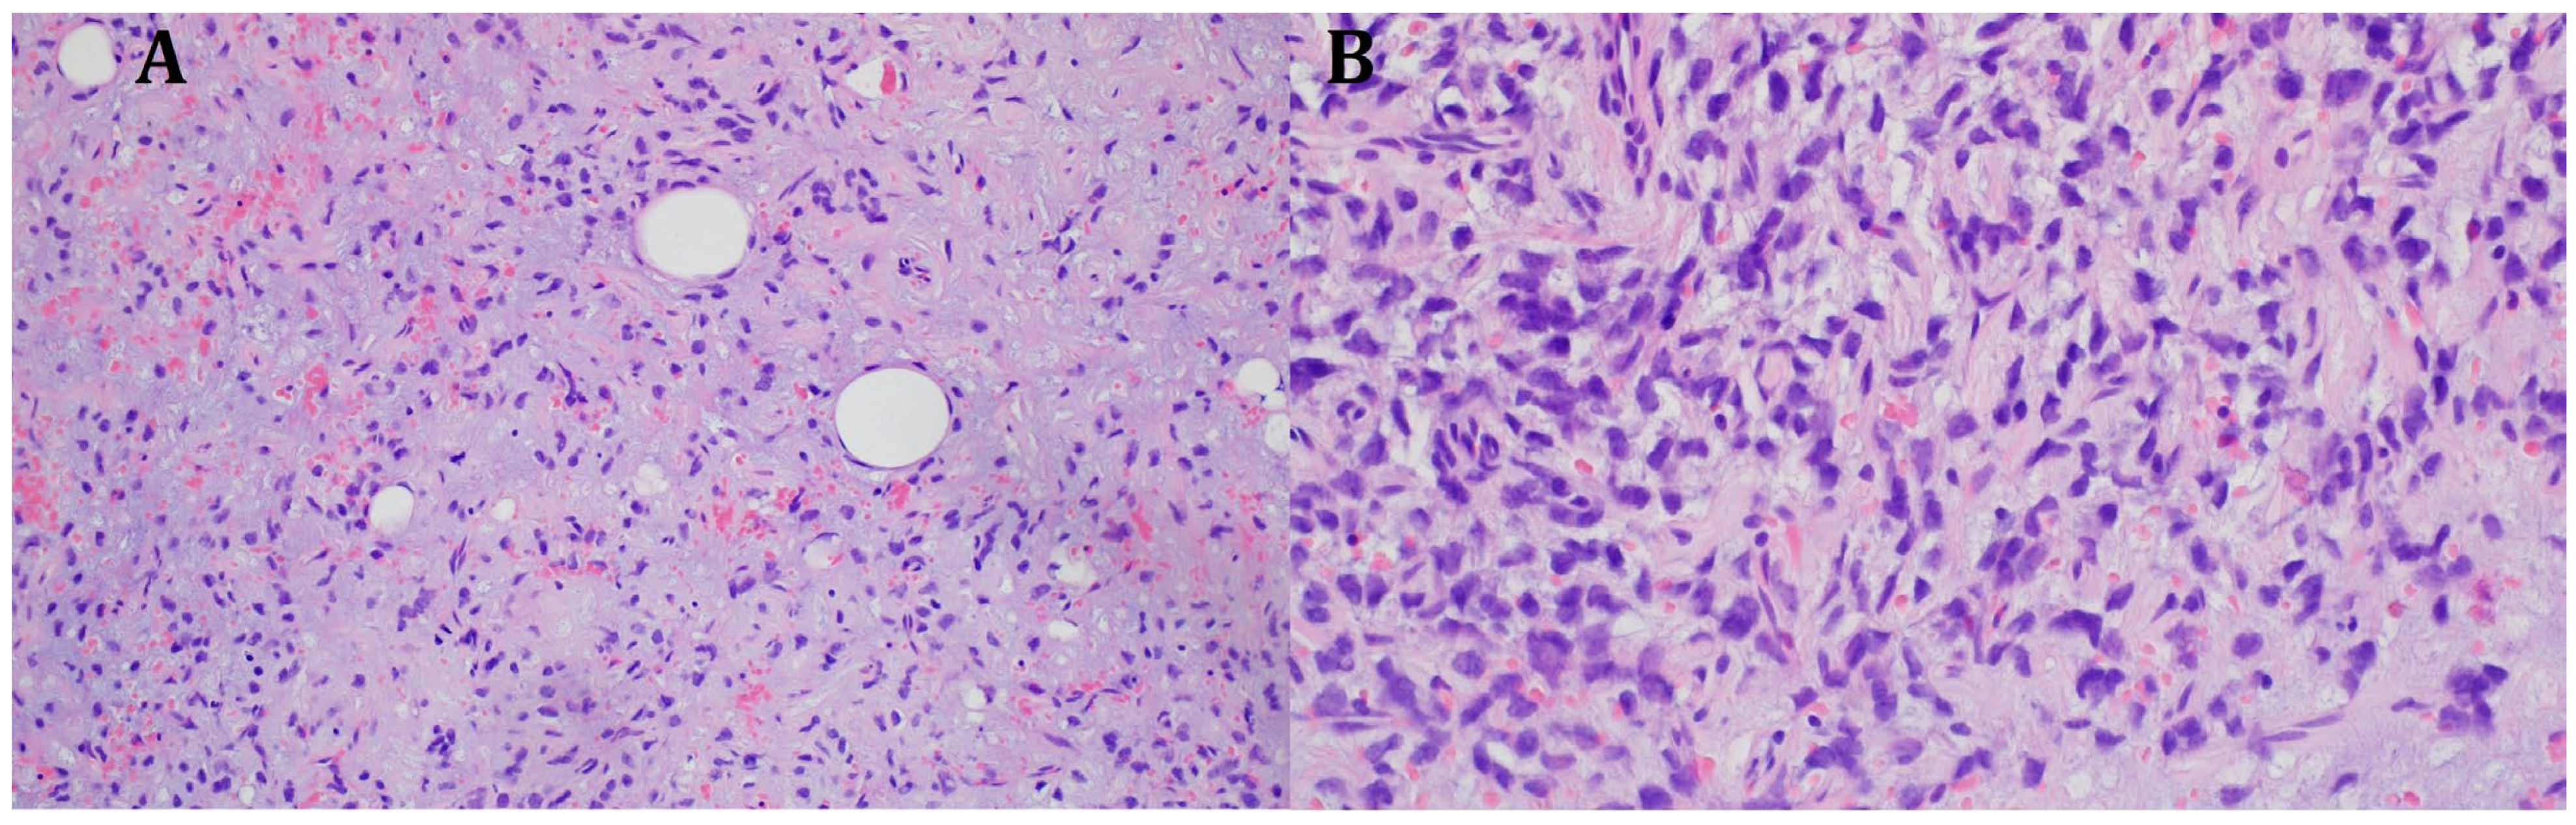

Empirical antibiotic therapy and compression therapy with elevation of the lower limb were introduced into the treatment. On the following day, the patient was qualified for open surgery performed by an experienced vascular surgeon. After an incision of the skin at the tumor level, at a length of 20 cm, an abundant mucous mass of about 600 g was detected infiltrating the quadriceps muscle of the thigh. No hematoma was found. The abnormal mucinous tissue was removed, and the thigh wound was sutured, leaving a drain. The procedure was uncomplicated, but the lesion was not removed in its entirety due to deep infiltration of the quadriceps muscle. In magnetic resonance imaging (MRI) of both thighs after surgical treatment, in the proximal part of the thigh, in the long adductor muscle, a nodular lesion measuring 138 × 89 × 71 mm having numerous internal septa was visible. The lesion was heterogeneous, with an increased signal in T2-weighted and PD-weighted images (Figure 3).

Figure 3.

MRI imaging of a massive right thigh tumor. (A) shows a coronal T2-weighted image, and (B) shows an axial contrast-enhanced T1-weighted image. The signal intensity of the tumor is very bright on the T2-weighted image (A), suggesting that the tumor contains myxoid parts. The contrast-enhanced T1-weighted image shows a strong contrast enhancement of the tumor (B) (Philips MR 7700, 3.0 T; Philips, Cambridge, USA).

The histopathological blocks from the operation were then re-analyzed in Warsaw. A FISH DDIT3 test and an additional IHC test were ordered. In the assessment of rearrangements within the DDIT3 gene, 95% of the examined cells were confirmed to be neoplastic. Tumors having round cell components higher than 5% of all tumor volumes were considered high grade (9% in this case). The below image (Figure 4) indicates rearrangements within the DDIT3 gene (12q13). In addition, the IHC confirmed SOX 11 (+). The FISH test results confirmed the diagnosis of myxoid liposarcoma. Due to the focally increased cellularity of the lesion, the diagnosis was changed to high-grade MLPS FNCLCC (Federation Nationale de Centros de Lutte Contre le Cancer) Grade 2 (G2) (Figure 4). In a chest CT scan, MRI of both lower limbs, abdominal—pelvic CT, and MRI of the whole body, there were no signs of metastases (M0 N0). The treatment plan changed during the preparation of this article. The first plan was to prepare the patient for a specific expert orthopedic oncology operation; however, after seeing the NGS and FISH results and changing the diagnosis to high-grade myxoid liposarcoma, an oncological committee review (tumor board review) was performed. This tumor board always includes a surgeon specializing in the relevant area, a clinical oncologist, a geneticist, a radiation therapist, and a chemotherapist. The decision was to perform neoadjuvant radiotherapy and chemotherapy before the operation (Figure 3). The patient gave written consent to publish the description of her case.